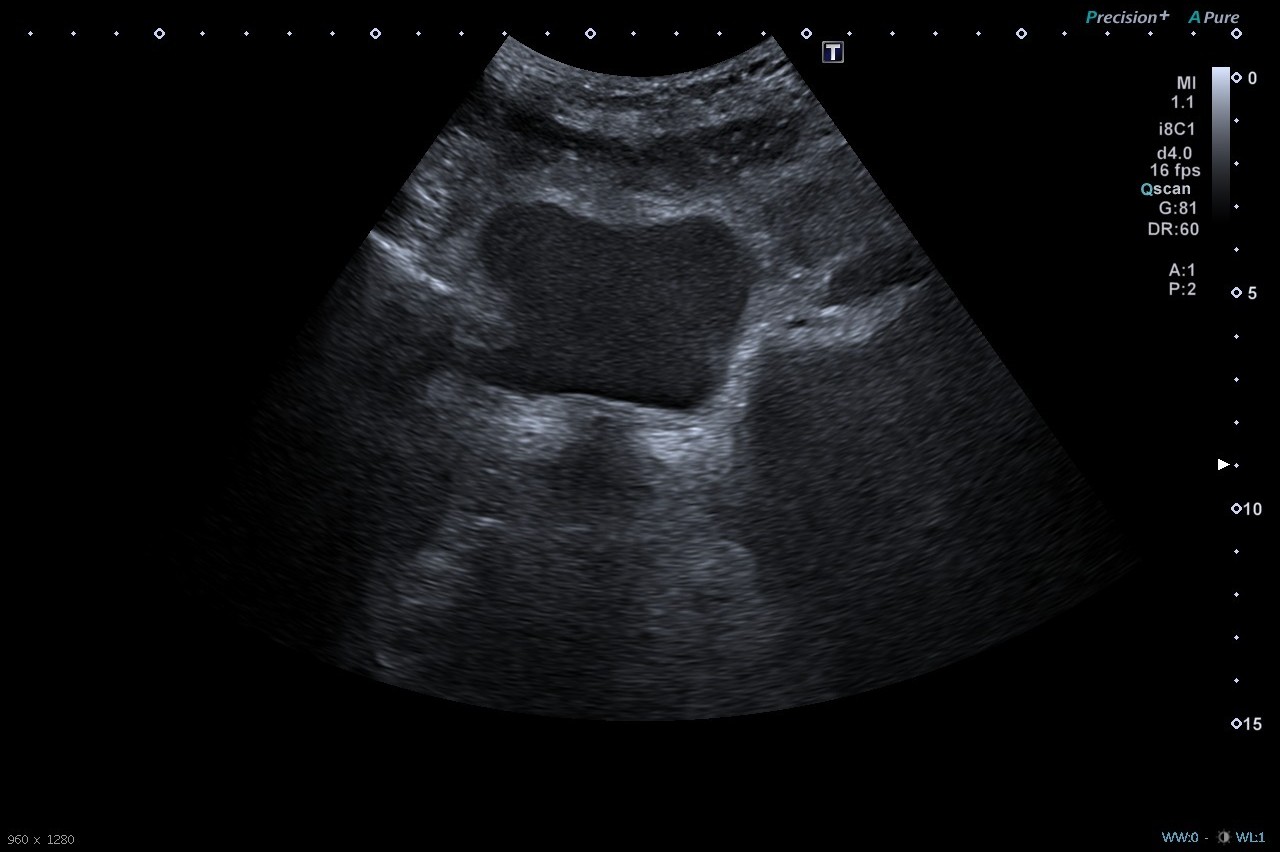

Hombre de 69 años que acude al CS por epigastralgia irradiada hacia hipocondrio izquierdo, náuseas y vómitos de <24 h de evolución. Asocia síndrome miccional y molestias en hipogastrio, hiporexia y coluria, sin fiebre u otra sintomatología. Dada ausencia de mejoría tras analgesia es derivado a Urgencias Hospitalarias. A su llegada dolor persistente y mal estado general. A la exploración física presenta palidez cutánea y deshidratación, abdomen doloroso a la palpación en región epigástrica e hipogástrica e irradiación hacia fosa renal izquierda.

Diagnóstico: Ureterohidronefrosis grado 3. Pancreatitis aguda de origen biliar.

El paciente ingresa en Digestivo por diagnóstico de pancreatitis aguda, con seguimiento simultáneo por Urología. Se realiza CPRE sin incidencias y posteriormente desarrolla una IRA prerrenal secundaria a proceso neoproliferativo renal. Se decide nefrouretectomía radical derecha.